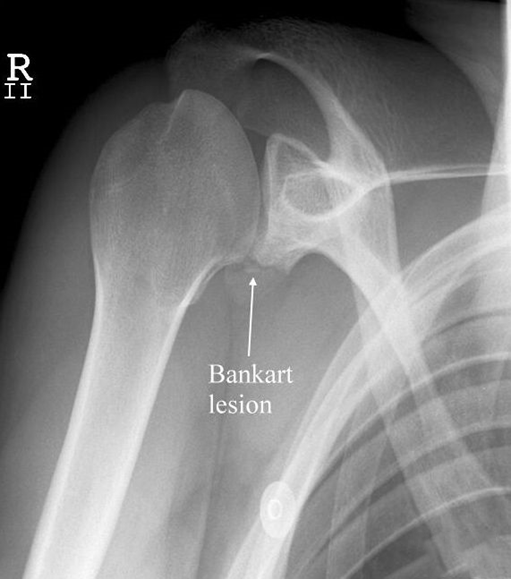

(1)bankart骨折

bankart 骨折指肩关节盂前下边缘骨折,伴或者不伴有肩关节前脱位。是肩关节盂唇前下方在前下盂肱韧带复合体附着处的撕脱性损伤。因肩关节前脱位引起,是造成习惯性前方不稳定和脱臼的基本损伤。